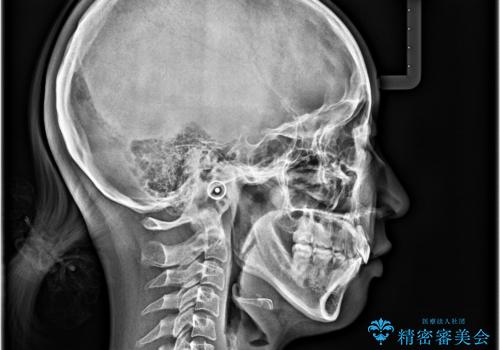

- 上顎前歯が飛び出していて唇がうまく閉じられないとのことで来院された患者様です。

くちばしのように前歯が突出していたため、口元を積極的に引っ込めるために、上下左右の小臼歯4本を抜歯することとしました。

また、上顎歯列が下顎に対して前方位に位置していたため、補助装置を用いて上顎歯列を後方に移動させ、より積極的に口元を下げるようにしました。